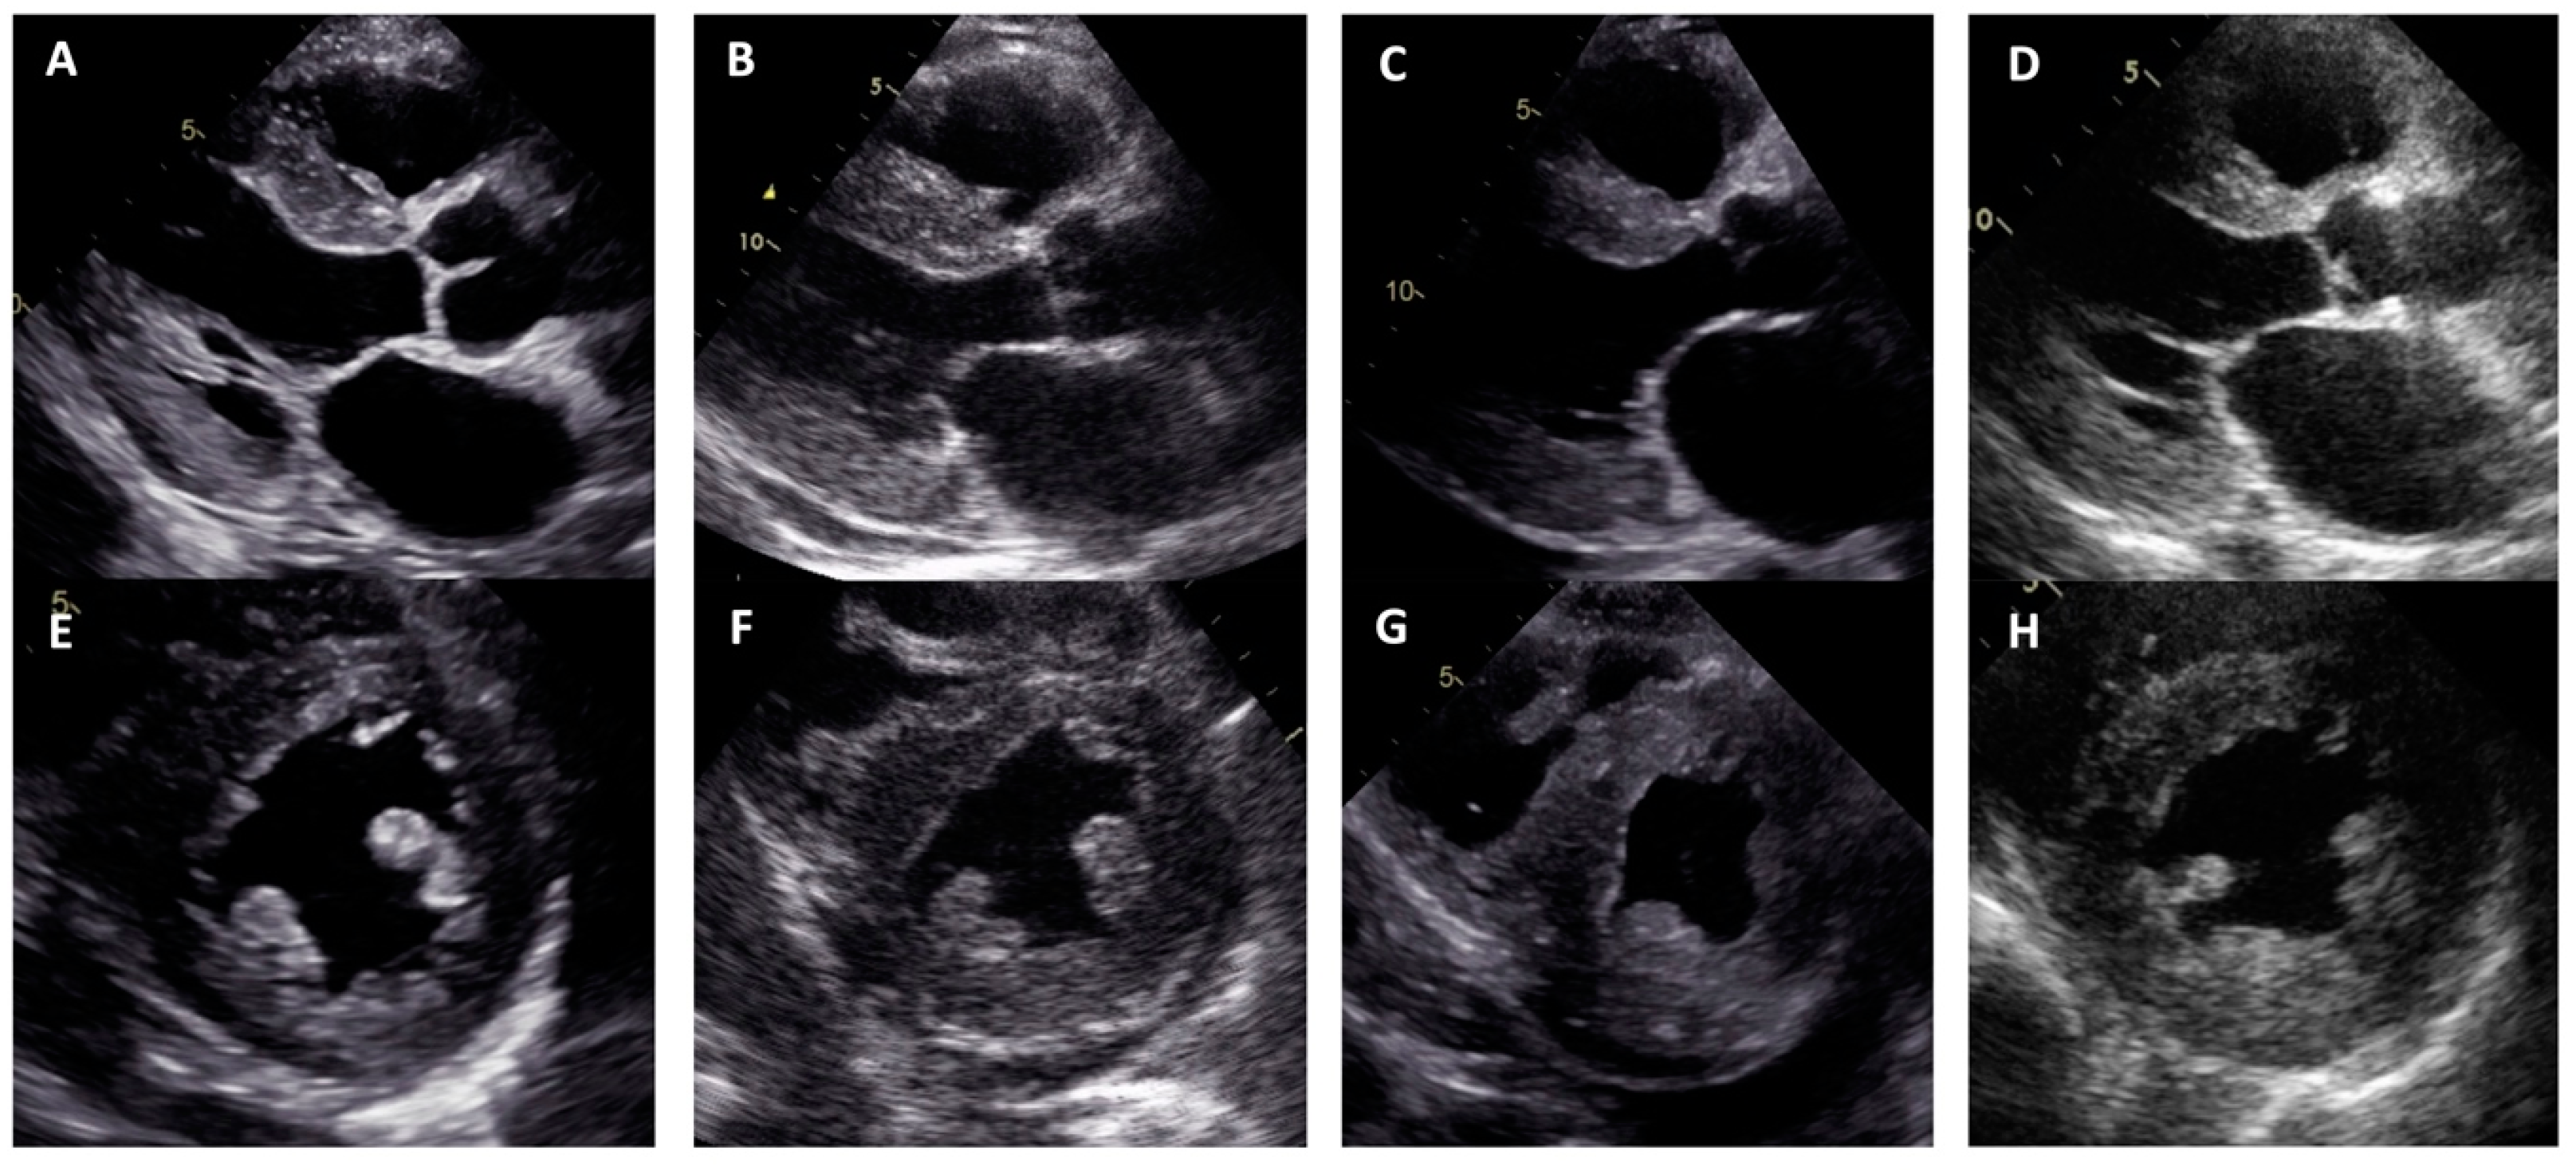

| LV hypertrophy | Concentric | Concentric | Concentric | Concentric |

| Maximal wall thickness (mm) | 13 | 21 | 14 | 19 |

| LVEF (%) | 67 | 10 | 55 | 40 |

| Restrictive LV filling pattern | - | + | + | + |

| Increased RV wall thickness | + | + | - | + |

| Pericardial effusion | - | + | - | - |